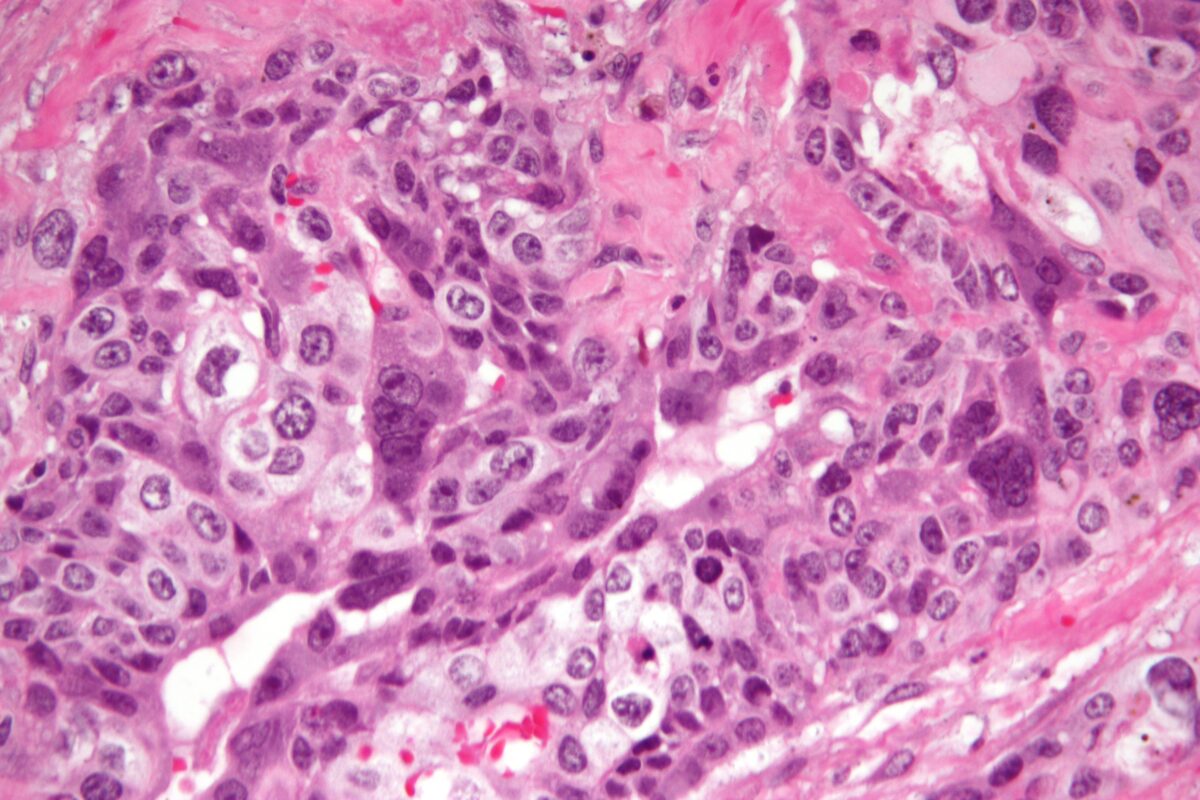

Ảnh trên: Ung thư nguyên bào nuôi (Choriocarcinoma)

– Ung thư nguyên bào nuôi (Choriocarcinoma): Đây là một dạng ung thư ác tính, hiếm gặp nhưng có khả năng di căn nhanh.

May mắn thay, theo Viện Ung thư Quốc gia Hoa Kỳ, ngay cả khi thai trứng tiến triển thành ung thư, bệnh vẫn có tỷ lệ chữa khỏi rất cao nếu được phát hiện sớm và điều trị bằng hóa trị liệu.